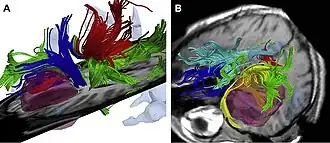

High resolution data acquired on 3-Tesla magnet and post-processed using automated tracking procedure.

High resolution data acquired on 3-Tesla magnet and post-processed using automated tracking procedure. -

High-dimensional white matter atlas generation and group analysis: result of automatic segmentation of novel subjects.

High-dimensional white matter atlas generation and group analysis: result of automatic segmentation of novel subjects. -